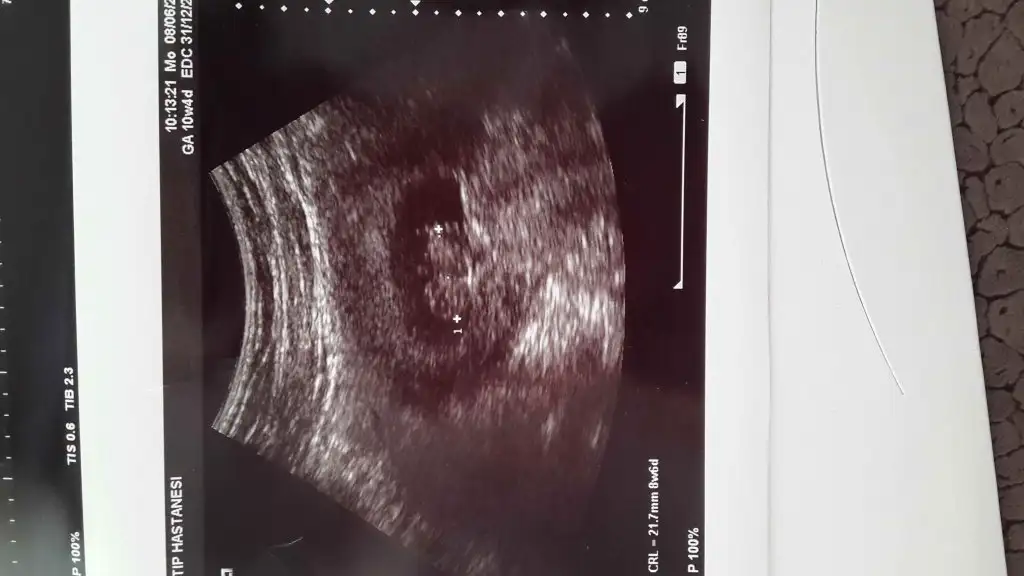

teyzeleri bakin benim melegime maşallah

Oooooyy oyyy oyyy teyzeleri yer onu :) Maşallah ya ap açık seçiliyor her yeri :) Allah'm cuma günü gelsin artık bende minnoşumu göreyimm